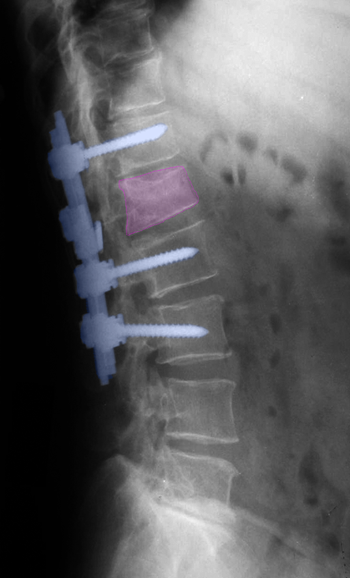

Μια άλλη μέθοδος σπονδυλοδεσίας, με την ίδια οπίσθια προσπέλαση, είναι η τοποθέτηση μεσοσπονδυλίων εμφυτευμάτων τύπου PLIF, η οποία όμως απαιτεί πάντα οσφυϊκή δισκεκτομή γιατί η τοποθέτηση τους γίνεται στη θέση του αφαιρεθέντος μεσοσπονδύλιου δίσκου. Τα εμφυτεύματα αποτελούνται από τιτάνιο ή ειδικό πολυμερές πλαστικό και χρήζουν και αυτά συνοδεία οστικού μοσχεύματος για να επιτευχθεί οστεοσύνθεση. Η δυνατότητα ανάταξης ανατομικής διαταραχής και σταθεροποίησης είναι όχι μεγάλη με τη βοήθεια αυτής της μεθόδου και γι' αυτό συνδυάζεται συχνά με οπίσθια διαυχενική σπονδυλοδεσία.